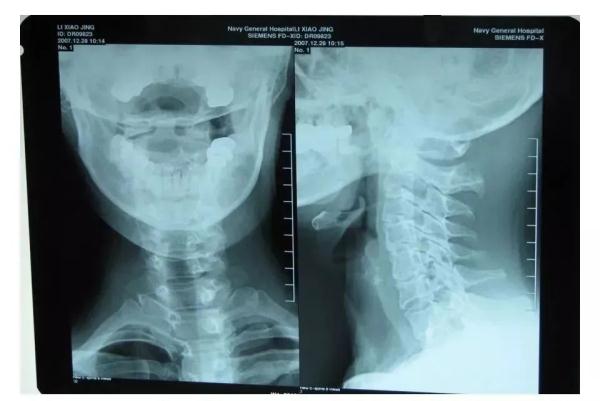

王建之经过阅片查体,明确徐大爷的晕厥可能和颈椎病有关,经过抽丝剥茧,终于找到晕厥的元凶:寰枢关节不稳

寰枢关节不稳

一般指颈椎的第一和第二关节

周围的结构遭到破坏,

缺乏稳定连接的寰枢关节。

患者可出现头晕、恶心、目眩、颈部僵硬、

颈部疼痛、头痛、行走不稳等症状。